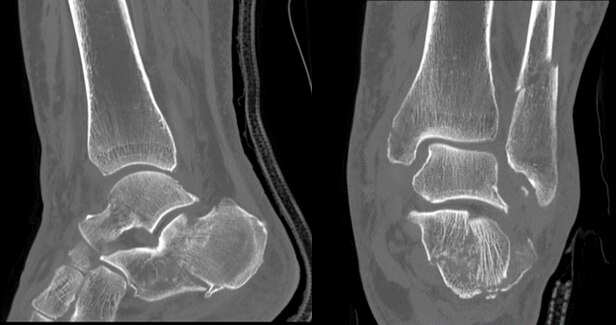

ハイレゾリューションモードが有効であった足関節の症例を提示します。

高分解能モードを使用することにより、骨梁まではっきりと画像化することができます。

本症例は複数の骨が骨折をしている症例ですが、どの骨においても細かな骨折線や骨片まで描出することができています。